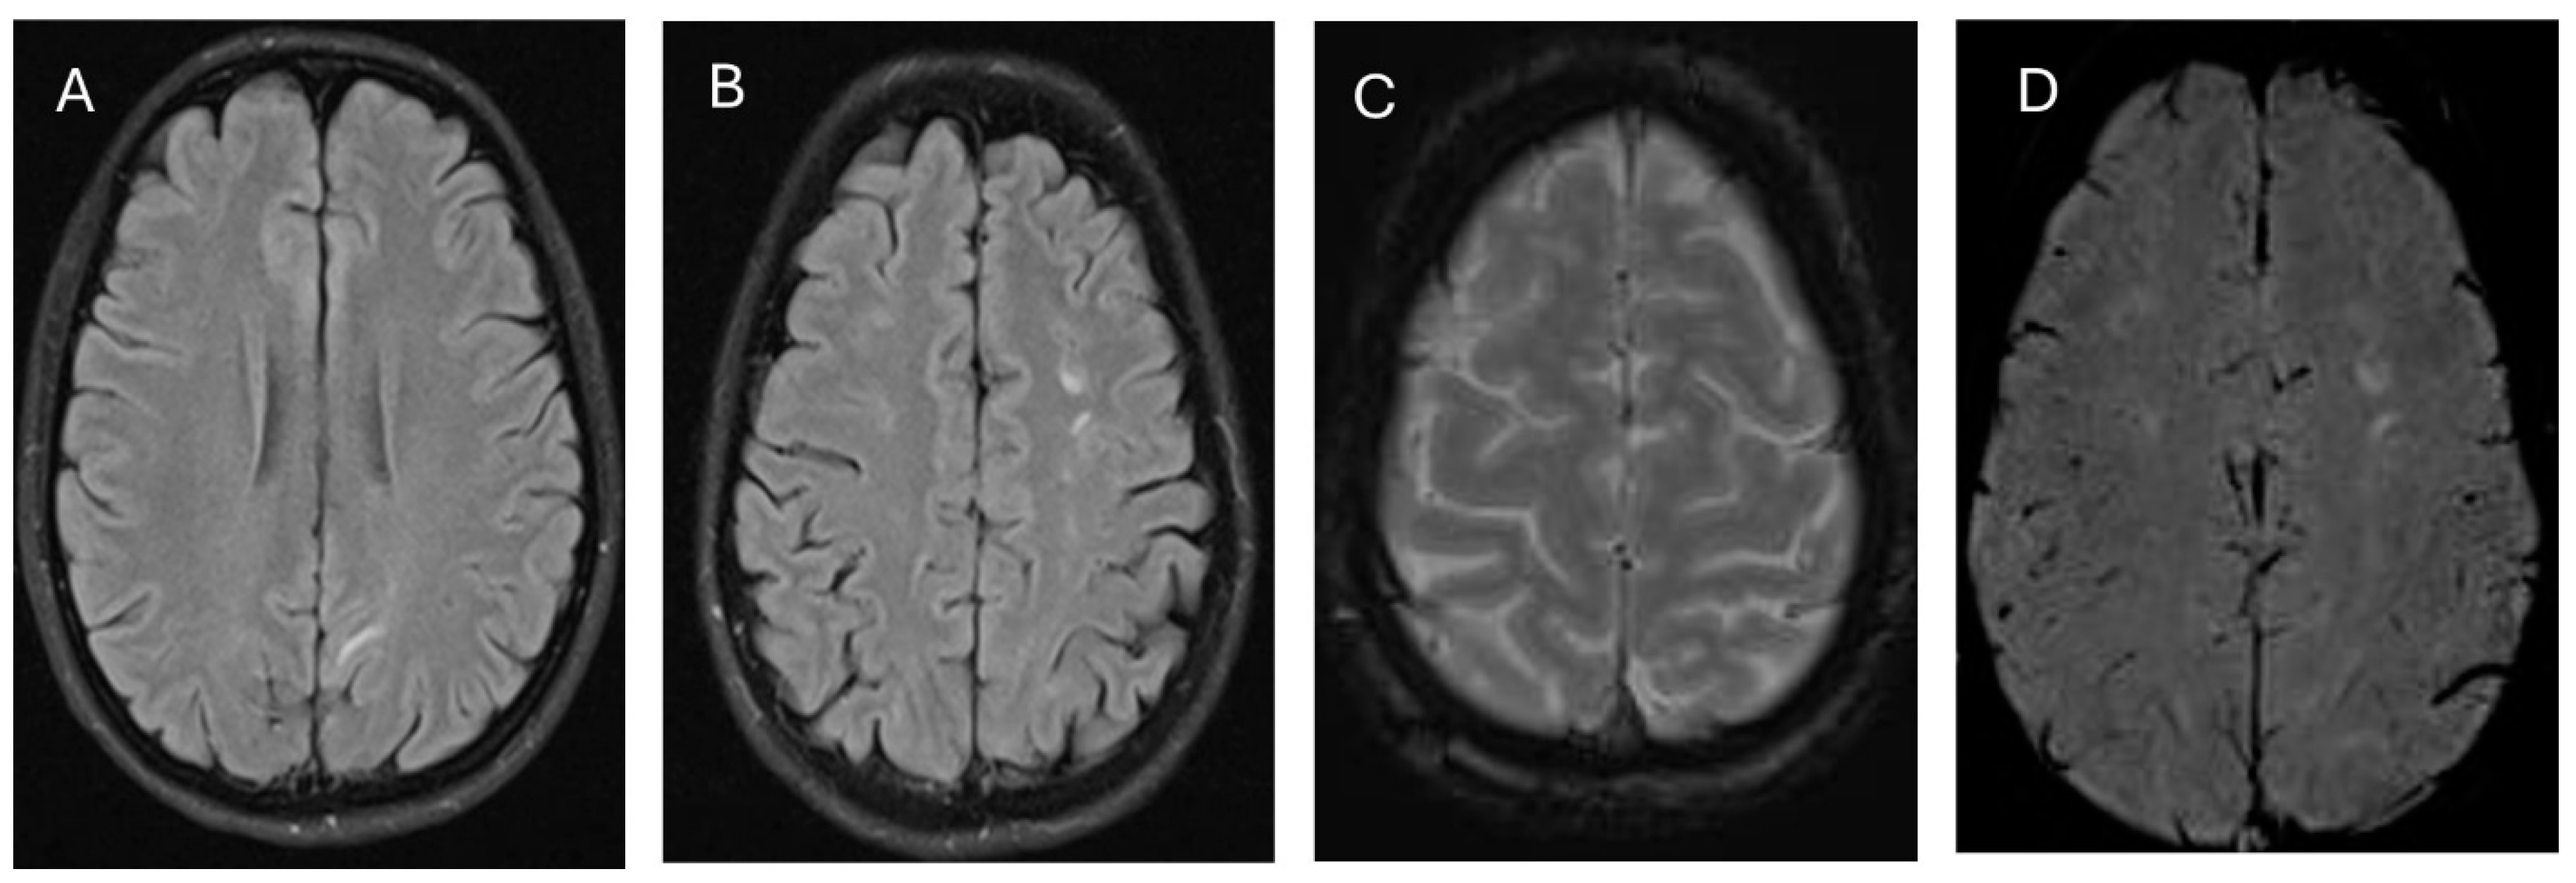

2. Case Presentation